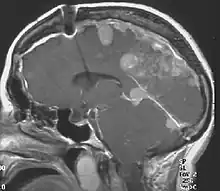

Neurofibromatosis type II (also known as MISME syndrome – multiple inherited schwannomas, meningiomas, and ependymomas) is a genetic condition that may be inherited or may arise spontaneously, and causes benign tumors of the brain, spinal cord, and peripheral nerves. The types of tumors frequently associated with NF2 include vestibular schwannomas, meningiomas, and ependymomas. The main manifestation of the condition is the development of bilateral benign brain tumors in the nerve sheath of the cranial nerve VIII, which is the "auditory-vestibular nerve" that transmits sensory information from the inner ear to the brain. Besides, other benign brain and spinal tumors occur. Symptoms depend on the presence, localisation and growth of the tumor(s). Many people with this condition also experience vision problems. Neurofibromatosis type II (NF2 or NF II) is caused by mutations of the "Merlin" gene,[2] which seems to influence the form and movement of cells. The principal treatments consist of neurosurgical removal of the tumors and surgical treatment of the eye lesions. Historically the underlying disorder has not had any therapy due to the cell function caused by the genetic mutation.

NF2 is a genetically transmitted condition. Diagnosis is most common in early adulthood (20–30 years); however, it can be diagnosed earlier. NF2 can be diagnosed due to the presence of a bilateral vestibular schwannoma, or an acoustic neuroma, which causes a hearing loss that may begin unilaterally.[14] If a patient does not meet this criterion of diagnosis, they must have a family history of NF2, and present with a unilateral vestibular schwannoma and other associated tumors (cranial meningioma, cranial nerve schwannoma, spinal meningioma, spinal ependymomas, peripheral nerve tumor, spinal schwannoma, subcutaneous tumor, skin plaque). This being said, more than half of all patients diagnosed with NF2 do not have a family history of the condition.[14] Although it has yet to be included into clinical classification, peripheral neuropathy, or damage to the peripheral nerves, which often causes weakness, numbness and pain in the hands and feet, may also lead to a diagnosis of NF2. In children, NF2 can present with similar symptoms, but generally causes "visual disturbances (cataracts, hamartomas), skin tumors, mononeuropathhy (facial paresis, drop foot), symptomatic spinal cord tumors, or non-vestibular intracranial tumors".[14]

- Detection of bilateral acoustic neuroma by imaging-procedures